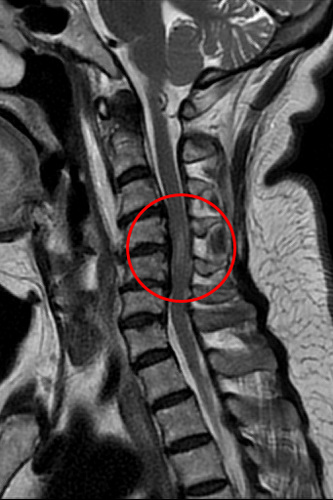

72歲徐姓婦人車禍後被送往花蓮慈濟醫院急診,神經外科部神經血管介入治療科主任李建輝會診時觀察到她僅能用腹式呼吸,加上手腳肌力僅剩二至三分,研判頸椎神經可能受損,進一步以磁振造影檢查確認是頸椎第四到六節之間的神經遭到骨刺壓迫,且已造成脊髓損傷。經李主任緊急以脊椎內固及融合微創手術治療,再經過中醫針灸和積極復健,病人於術後半個月即可下床,靠輔具行走,目前恢復良好。

李建輝主任表示,當時在急診看到婦人,除主述四肢癱軟無力,發現她一直在用腹式呼吸,無法自然呼吸,令他警覺有可能是頸椎神經受損,因為控制橫膈的神經就在頸椎附近,透過檢查果然是第四到六節的神經被壓迫,且能清楚看到她的骨刺壓迫已造成脊髓損傷,有癱瘓風險,須儘快手術清除和重建,提高恢復的可能性,隨即在隔天進行手術,清除突出的椎間盤後放入填充物,並用支架固定頸椎。

圖:磁振造影檢查結果顯示,72歲徐姓婦人頸椎第四到六節的神經被壓迫,且已造成脊髓損傷。